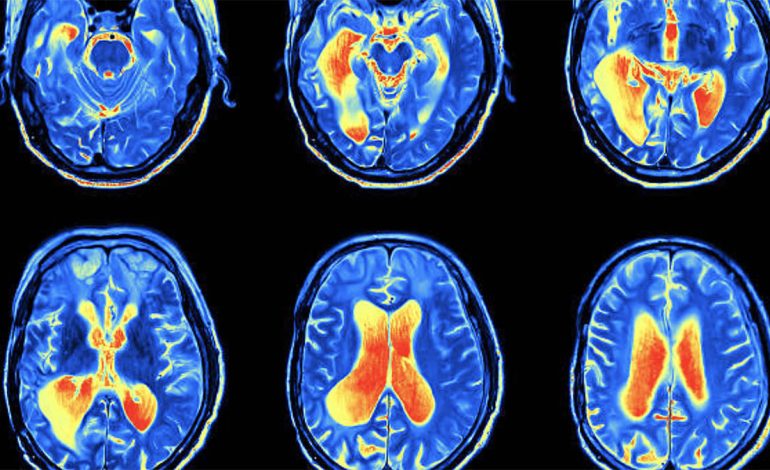

Alzhaimeri është një sëmundje që prek disa zona të trurit përgjegjëse për kujtimet dhe memorien.